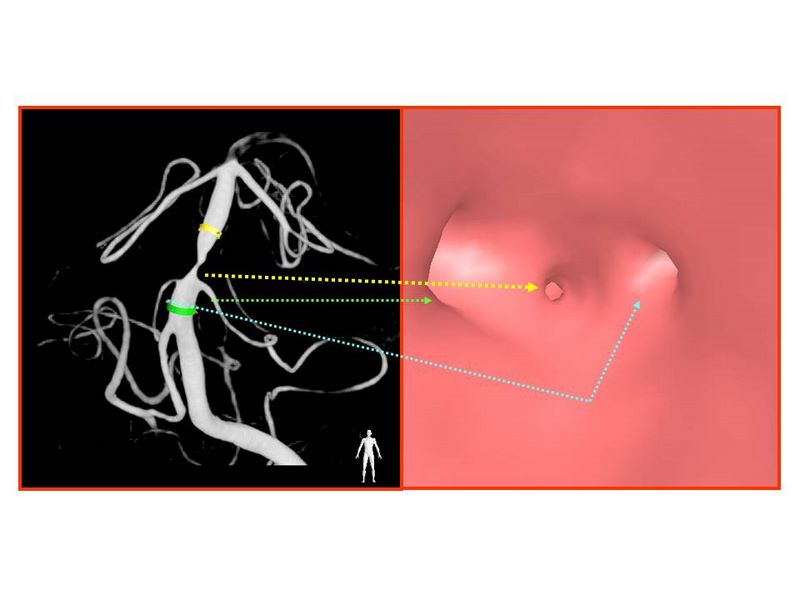

Estenosis Basilar